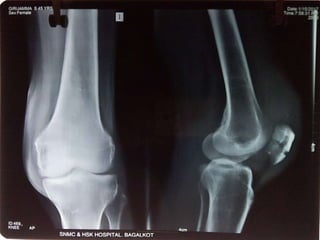

Investigations

X-RAY

X-RAY of left leg showing Fracture of patella